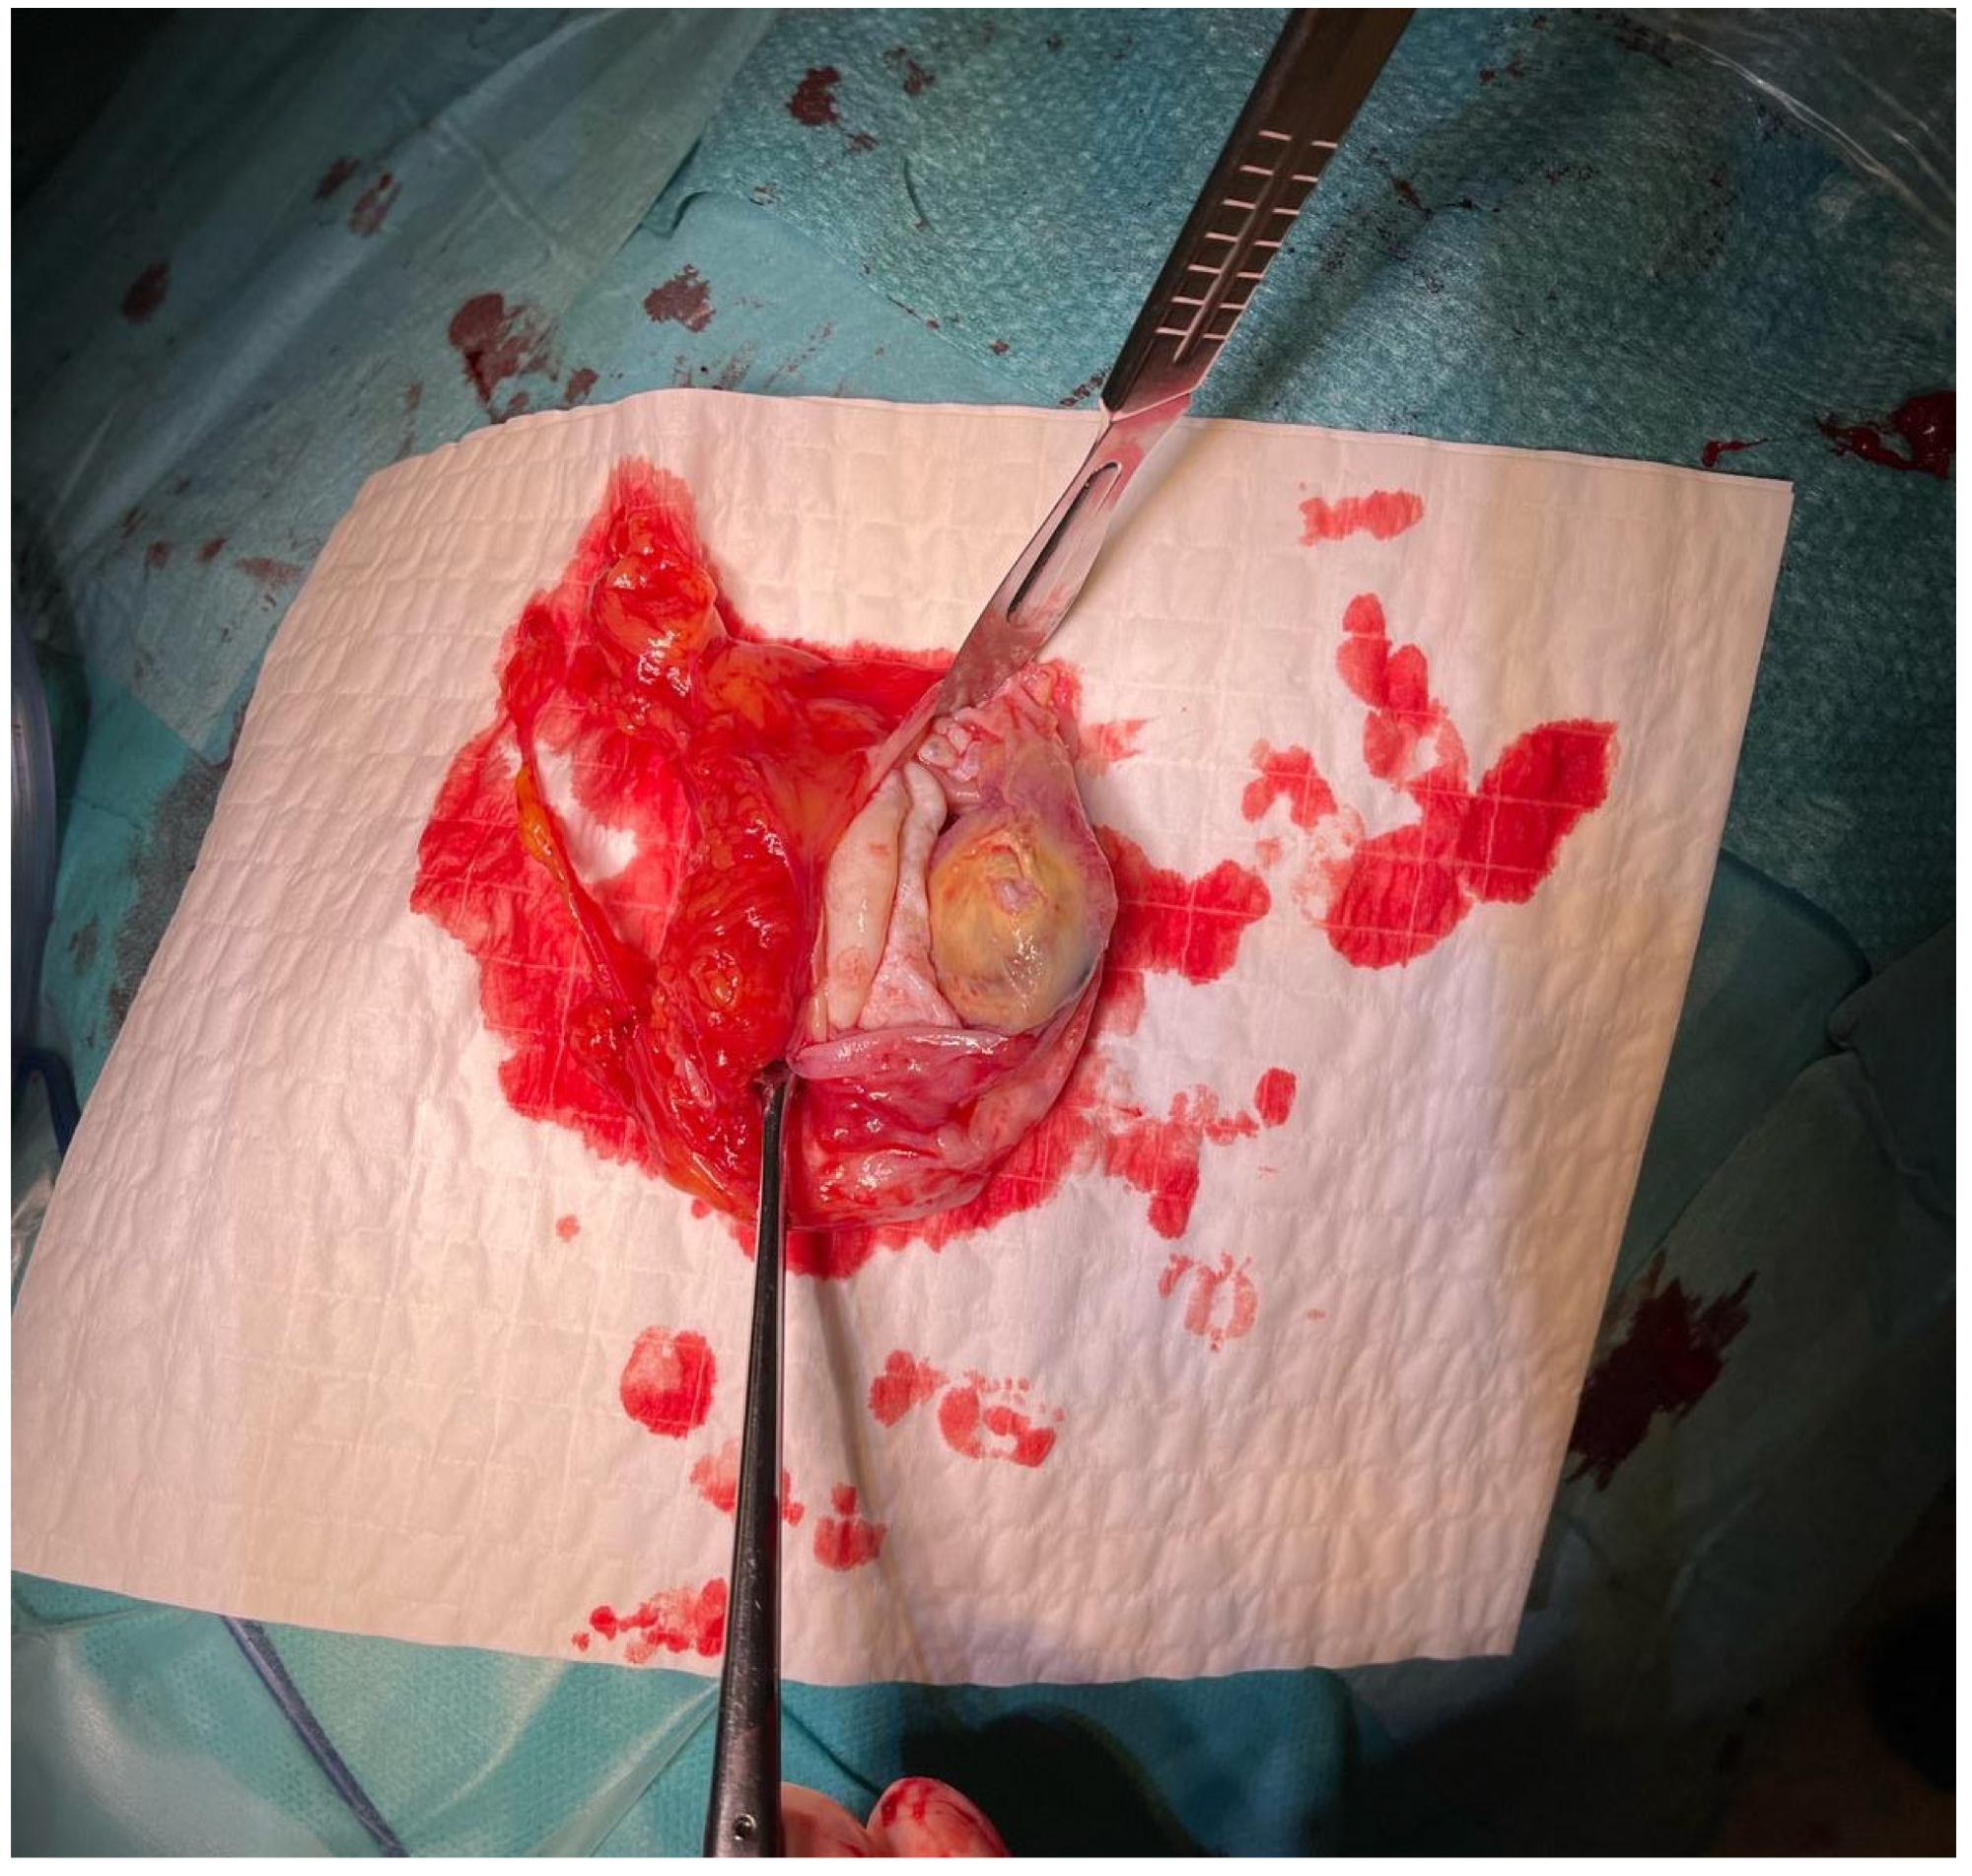

Upon admission, the patient underwent chest X-ray, which demonstrated well-defined consolidation in the left pulmonary hilum (Figure 2). An echocardiogram revealed that the lesion was not communicating with the heart muscle. However, it was adjacent to the pericardium.

Figure 2. Chest X-ray showing well-defined consolidation in the left pulmonary hilum. PA, posteroanterior position.